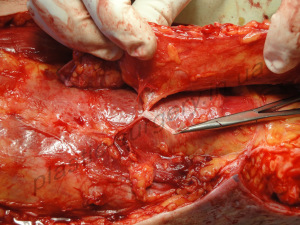

После предварительной локации допплером доминантного перфоранта в предполагаемой зоне формирования лоскута, в нижней 1/3 бедра, по задней поверхности был выкроен кожно-фасциальный лоскут размером 15х8 см. (рис. 5). Лоскут на перфоранте подколенной артерии ротирован на 180 градусов в область раневого дефекта подколенной ямки, где предварительно были иссечены патологические грануляции (рис. 6).

Рис. 5. Интраоперационное цифровое фото. Визуализируется выделенный перфорант подколенной артерии, кровоснабжающий лоскут (слева).

В клинике определена зона рассечения и иссечения рубцов в подколенной области, где после устранения контрактуры и выведения конечности в положение полного разгибания сформировался раневой дефект, площадью до 4 х 9 см., который не может быть закрыт путем сближения краев раны или выполнения стандартной Z-пластики (Рис. 11). Методом допплера лоцирован третий перфорант глубокой артерии бедра, выходящий на заднюю повехность кожного покрова бедра в его нижней 1/3) и намечен дизайн кожно-подкожно-фасциального перфорантного пропеллер лоскута (PPPF) на базе названного перфоранта (Perforator of the Profunda Femoris Artery Perforator – PFAP-3). После полной дессекции PFAP-3 лоскут поднят на ножке, включающей обозначенный перфорант, проведена его визуализация и определена жизнеспособность самого лоскута (Рис. 12).

Рис. 12. Цифровое интраоперационное фото раневого дефекта после полной дессекции и подъема кожно-подкожно-фасциального островкового PFAP-3 лоскута, определение его жизнеспособности (справа).